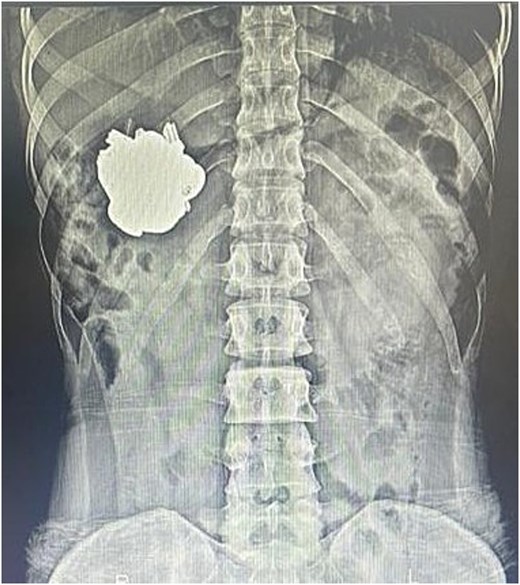

An emergency abdominal X-ray demonstrated a metallic mass localized to the left gastric region (Fig. 1). Preoperative laboratory investigations were unremarkable. Subsequent upper gastrointestinal endoscopy revealed multiple metallic foreign bodies—identified as keys—within the gastric lumen. The gastric mucosa showed minor ulcerations involving the cardia and body (Fig. 2).

Plain abdominal X-ray (anteroposterior view) showing a large metallic foreign body projected over the left upper quadrant, corresponding to the stomach. The object has well-defined borders and dense radiopacity, consistent with an ingested metallic component.